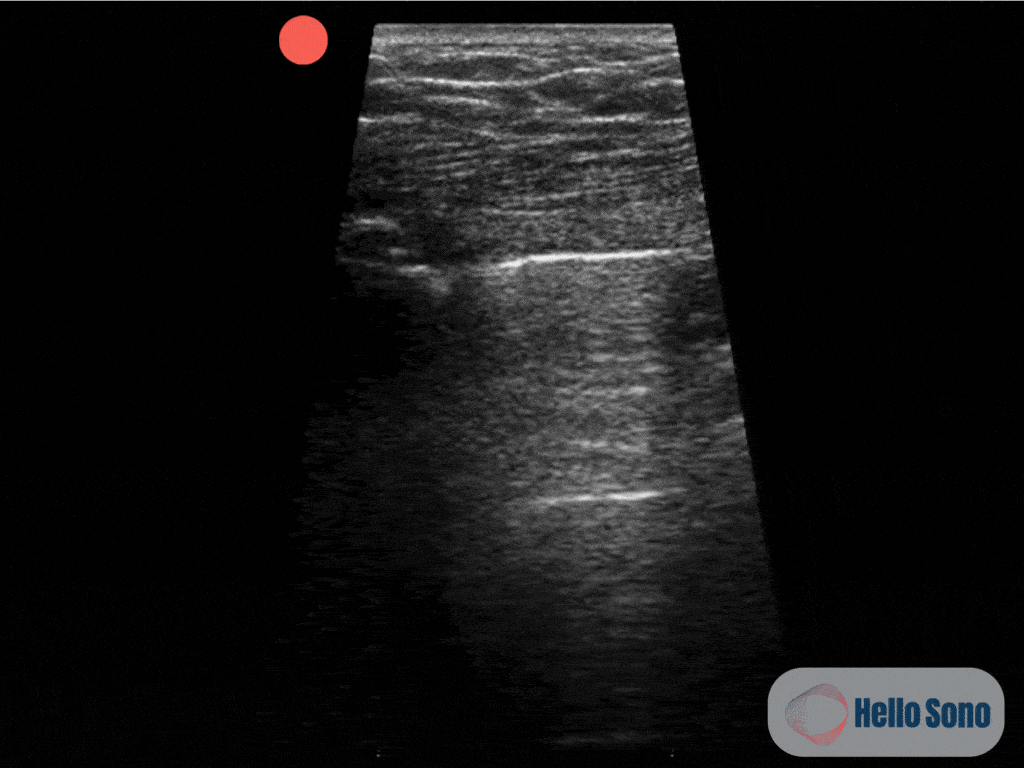

Clip 1: This ultrasound clip shows the apex of the right lung. The pleura appears as a bright white (hyperechoic) horizontal line near the top of the image. You can observe pleural sliding on the right side of the image, while the left side shows no sliding.

The ultrasound clip reveals a lung point, the exact location where normal lung with pleural sliding transitions to an area without sliding. This “on-off” pattern is pathognomonic for pneumothorax. On one side of the image, shimmering pleural sliding confirms lung apposition; on the other side, the absence of sliding confirms the presence of air in the pleural space.  See annotated clip (Clip 2).

Although complete absence of lung sliding may suggest a pneumothorax, it is not specific. Other conditions, such as pleural adhesions, large subpleural blebs, subpleural pneumonia, or scarring from prior infection or surgery, can also eliminate lung sliding. Therefore, identifying the lung point is key as it confirms the presence of a pneumothorax with high specificity.